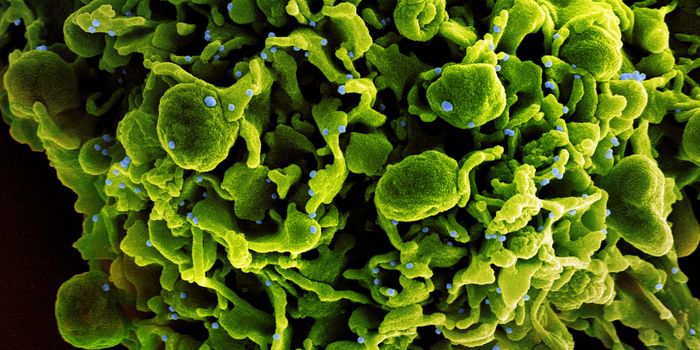

APR 04, 2022Cell & Molecular BiologyAbout 1.5 million new HIV infections are thought to have occurred last year, and while COVID-19 has dominated concerns a ...

FEB 21, 2022Cell & Molecular BiologyTwo people have been cured of HIV, and now, a US woman joins them. In this third case, stem cell transplants were being ...

NOV 30, 2021ImmunologyHIV is a master of disguise. Once the virus enters the body, it has a number of sophisticated mechanisms through which i ...

NOV 22, 2021MicrobiologyThough treatments are available, there is no cure or vaccine from HIV, which impacts about 38 million people worldwide. ...

SEP 06, 2021MicrobiologyHIV vaccines have remained elusive in part because the virus has a powerful ability to mutate, and there are so many str ...